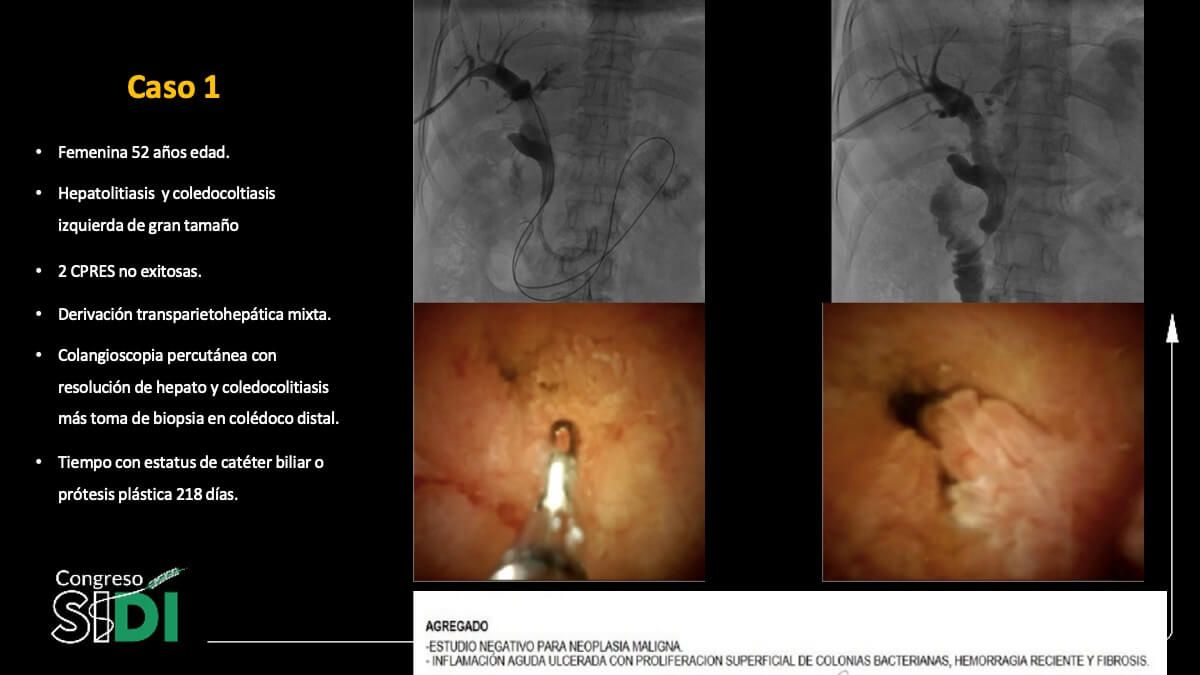

Cambios tisulares en el epitelio biliar inducidos por prótesis plásticas: Evidencia colangioscópica e histológica

Dr. Carlos Saldívar